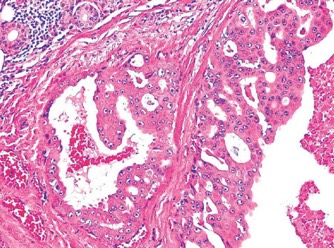

1063. Для представленной опухоли слюнных желез характерно агрессивное течение, внутрипротоковый рост и апокриновая дифференцировка